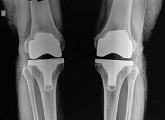

Endoprothetik des Kniegelenks

In den späten Stadien der Arthrose des Knies durch eine ausgeprägte Begrenzung der Bewegung begleitet, konstant starke Schmerzen, körperliche Unversehrtheit Verformung bis zur Genesung der einzige Weg ist der Ersatz des betroffenen Gelenks für eine künstliche - Endoprothetik.

Diese Methode ermöglicht es Ihnen, die richtige Form des Gliedes, eine vollständige Palette von Bewegung im Gelenke, zu entlasten ständige Schmerzen und Knirschen bei Bewegung und als Ergebnis wieder herzustellen, signifikant dem Patienten Lebensqualität zu verbessern.

Im Folgenden sind Röntgenaufnahmen und Fotografien, die die Strecke der Bewegung in der betroffenen Gelenke vor und nach der Operation veranschaulichen.